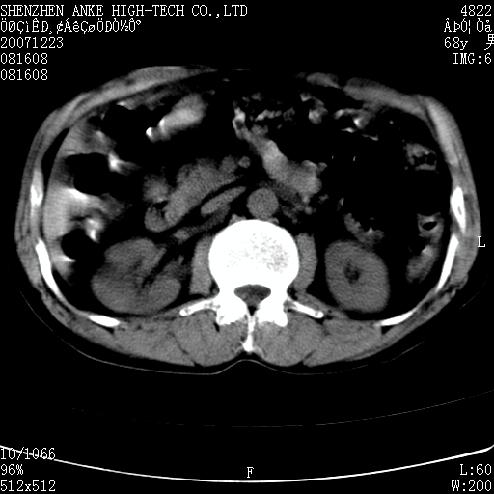

患者:男,63岁,2年前胆囊切除术后,现右上腹部剧烈疼痛近2天.

有无外伤史?右肾包膜下血肿可疑。

主要是问右肾有没有问题?患者无明显外伤史.

未见异常,病人差闭气,伪影较多.

肠道准备不好,干扰影大。

肠道气体伪影干扰太大了,应该是干扰所致,未见明显异常。

肠道准备不好,胃底后壁显示不清,右肾改变考虑为伪影。

请看第一张正位片,胸主动脉象有扩张,胸主动脉瘤?